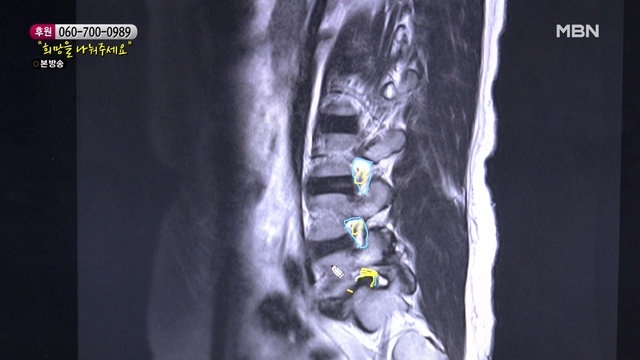

허리 상태가 많이 좋지 않은 엄마 MBN 220115 방송

허리 상태가 많이 좋지 않은 엄마

02:44허리가 아파 길에서 주저앉은 엄마 MBN 220115 방송